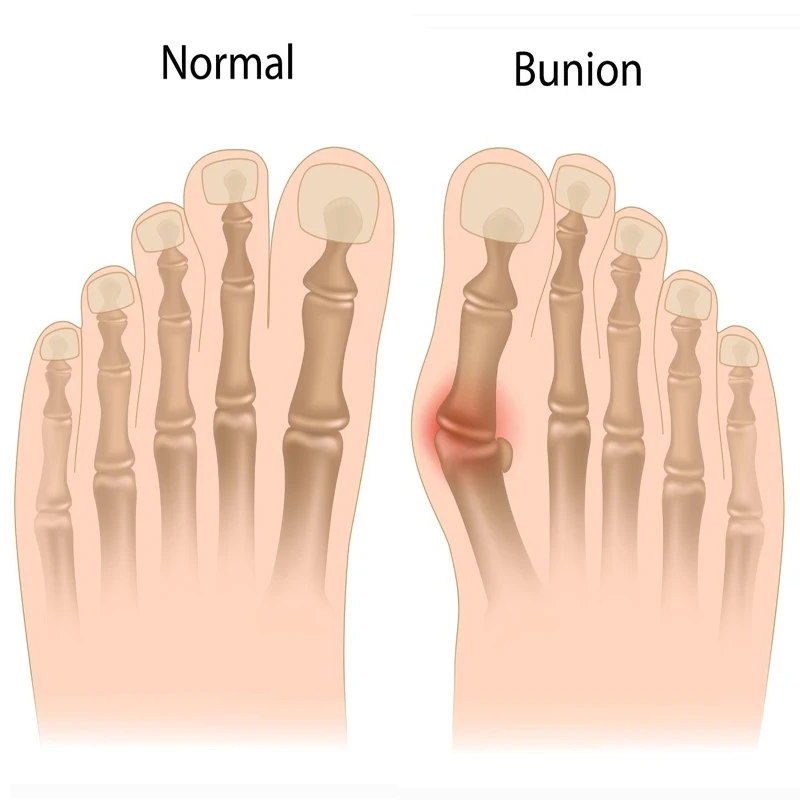

1Pair Soft Bunion Orthotics Splint Correction Valgus Pro System Class Medical Device Hallux Valgus Toe Separator Foot Care Tool